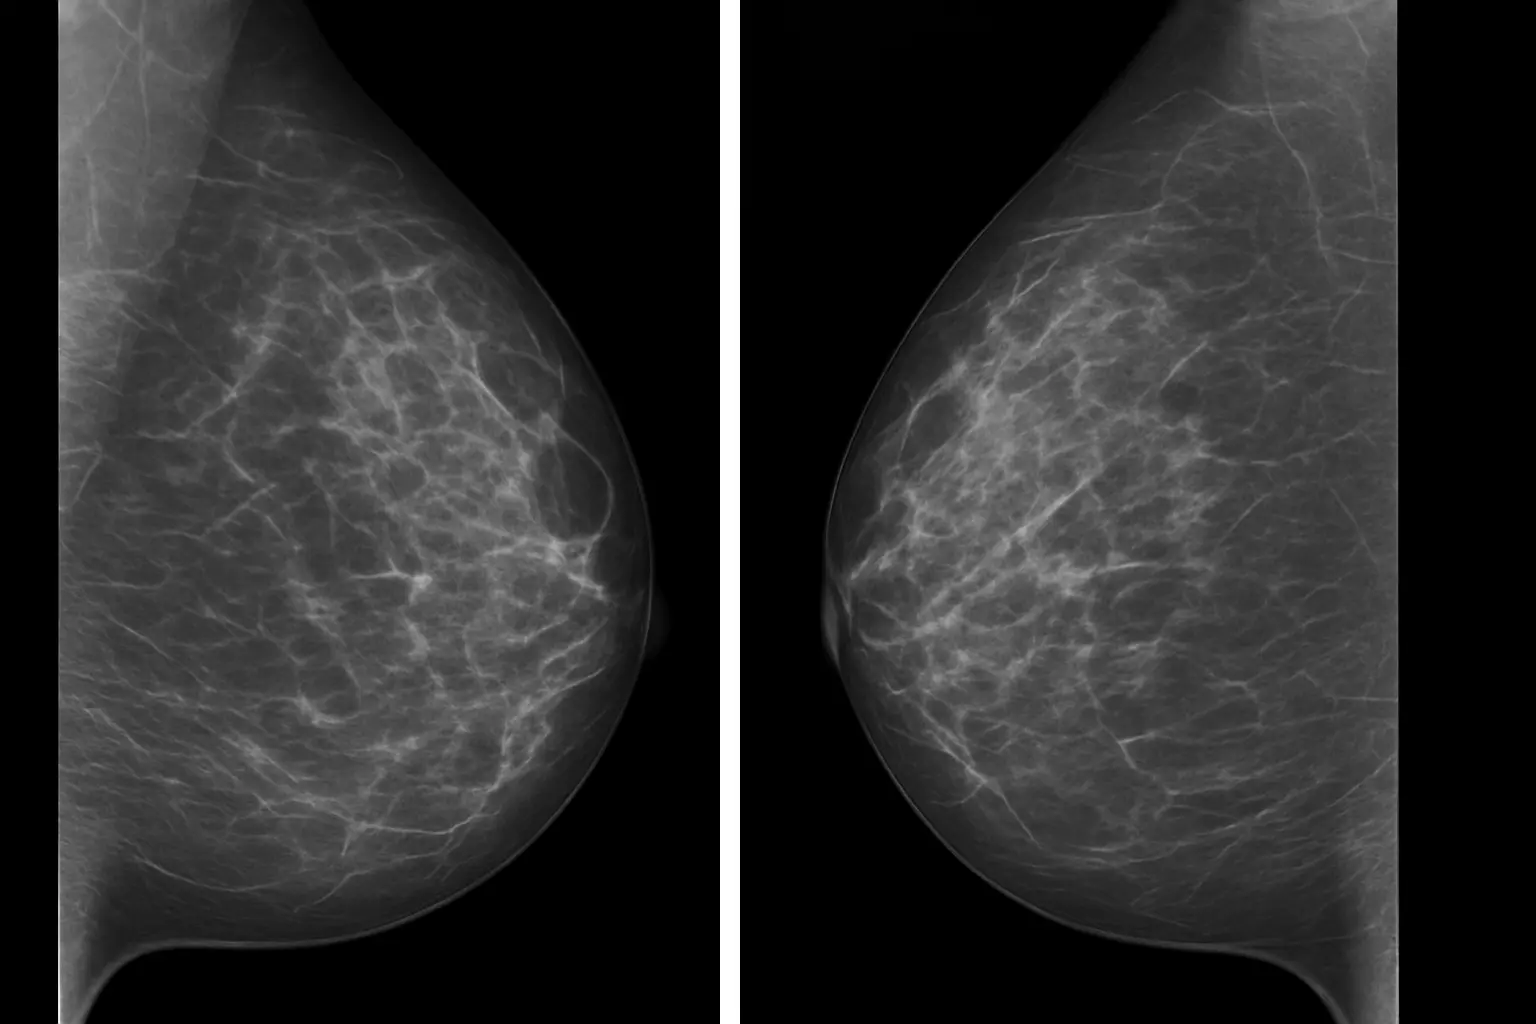

Breast density describes the mix of glandular/fibrous tissue and fat seen on a mammogram. It is reported in four categories:4,6

A: Almost entirely fatty

B: Scattered areas of dense tissue

C: Mostly dense

D: Extremely dense

Dense breasts (C or D) are very common and normal.

Why does density matter when it comes to mammograms?

Dense tissue can make cancers harder to see on a mammogram (also known as reduced sensitivity).1,2,4,6 Mammograms remain the most important screening method for detecting breast cancer4,6 and knowing your breast density helps you and your doctor decide if any additional screening options are appropriate for you.